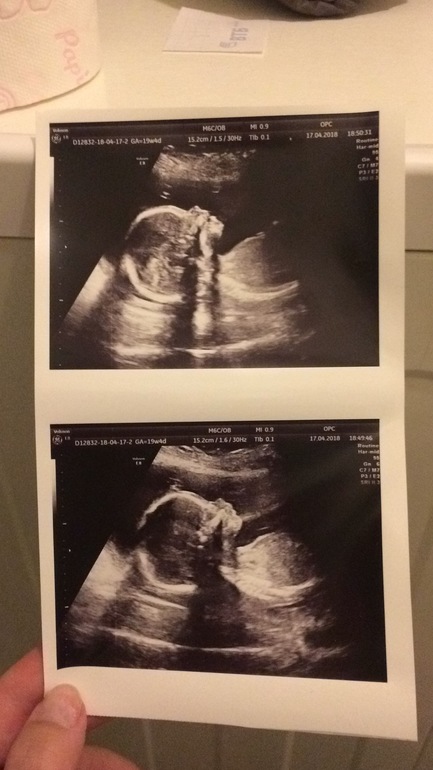

Девочки, всем привет! Срок 19,5 дней. Вчера был 2 скрининг ииииииииии можно закрашивать кружочек, у нас будет мальчиииииккк

Муж безумно рад и я тоже, но почему то была уверенна что девочка будет, уже и имя подобрали была бы АНИСИЯ и вещей дома куча девчачьих ничего не продавали и не отдавали)))И я вообще боюсь как это с мальчиками, у нас в семье несколько поколений рождались только девочки а тут такая радость, все безумно рады 😁 🙂 Но расстроилась я очень, так как 2 скрининг ставят гипоплазию кости носа. Норма на таком сроке 5,5 мм а у нас 3.5 мм. Отправляют второй раз на консультацию к генетику, но она будет опять предлагать взять пункцию, что это не понимаю. Вообще ну очень страшно. У меня, у мужа и у дочки маленькие носики, и узист сказала что может это и ничего страшного просто особенность такая.Притом что 1 скрининг и 2 скрининг проводились в разных местах и гипоплазию в обоих случаях ставили. Кто, что может сказать по этому поводу? Страшно ли это? или сильно не стоит переживать?